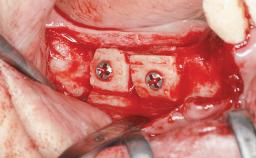

A 79-year-old female patient was referred to the Department of Periodontology of the University of Bern, Switzerland by her private dentist in May 2019. She had been rehabilitated in May 2005 with two tissue-level implants (Institut Straumann AG, Basel Switzerland) at sites 13 and 15, supporting a three-unit cemented fixed dental prosthesis (FDP). The metal-ceramic FDP had been cemented permanently with a glass-ionomer cement (Ketac Cem; 3M ESPE, Seefeld, Germany). Implant 13 had been diagnosed with peri-implant mucositis by the referring dentist in the course of regular supportive therapy. The patient was in good general health, did not smoke, and exhibited good self-performed plaque control.